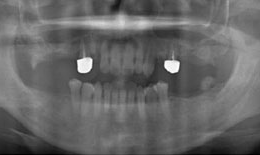

インプラント症例(6) 52歳 女性

治療後

下顎

インプラントを4本埋め込んで、セラミックスクラウンを被せた